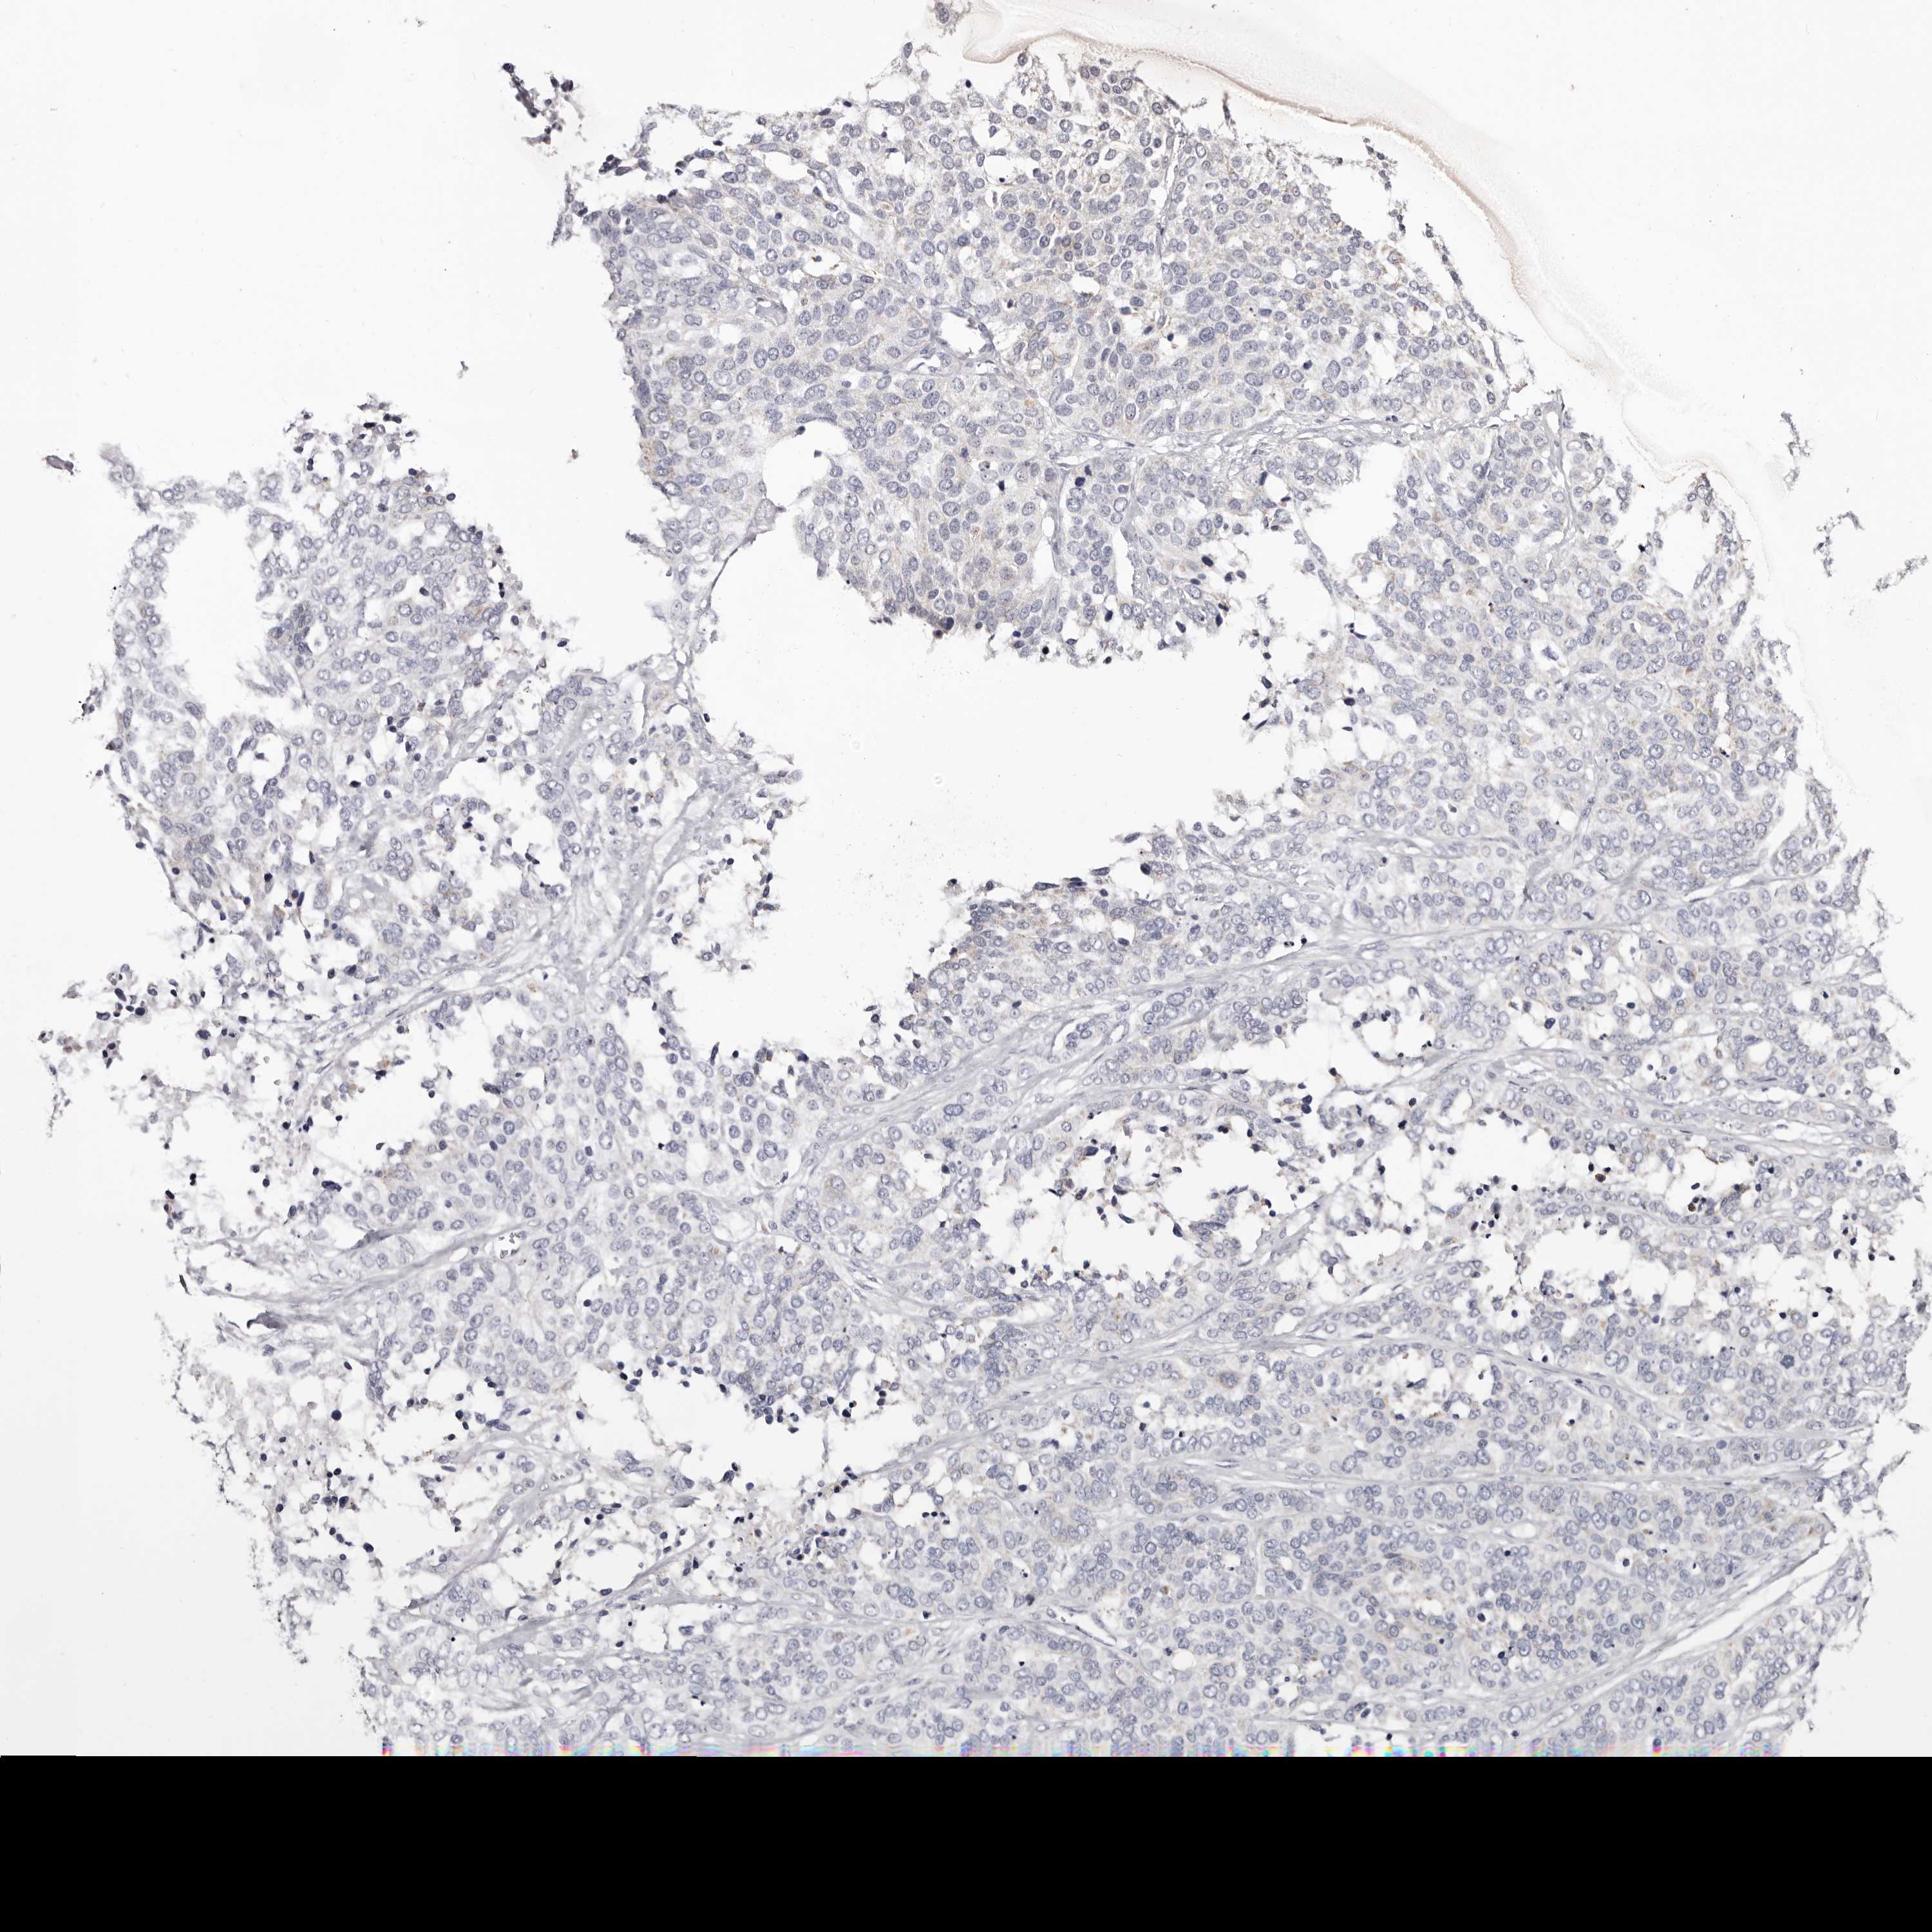

OVARIAN CANCER - Protein expressioni

A mouse-over function shows sample information and annotation data. Click on an image to view it in a full screen mode. Samples can be filtered based on level of antibody staining by selecting one or several of the following categories: high, medium, low and not detected. The assay and annotation is described here.

Note that samples used for immunohistochemistry by the Human Protein Atlas do not correspond to samples in the TCGA dataset.

Antibody stainingi

Antibody staining in the annotated cell types in the current human tissue is reported as not detected, low, medium, or high, based on conventional immunohistochemistry profiling in selected tissues. This score is based on the combination of the staining intensity and fraction of stained cells.

Each image is clickable and will lead to virtual microscopy that enables deeper exploration of all samples and also displays staining intensity scores, fraction scores and subcellular localization as well as patient and tissue information for each sample.

Antibody HPA007845

Antibody HPA026823

Antibody CAB015170

Staining

High

Medium

Low

Not detected

Cystadenocarcinoma, serous, NOS

Carcinoma, endometroid

Cystadenocarcinoma, mucinous, NOS

Carcinoma, NOS